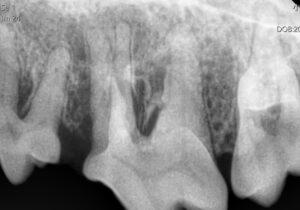

【📷 歯科レントゲン写真】

全身麻酔下で歯科レントゲン検査を行ったところ、右の大きな奥歯に根尖病変が確認されました。

内歯瘻とは、歯の内部で起きた感染が、歯ぐきを突き破って膿として排出される状態です。

この病気の厄介な点は、

・歯が折れていなくても起こる

・外からは小さなできものにしか見えない

という点です。